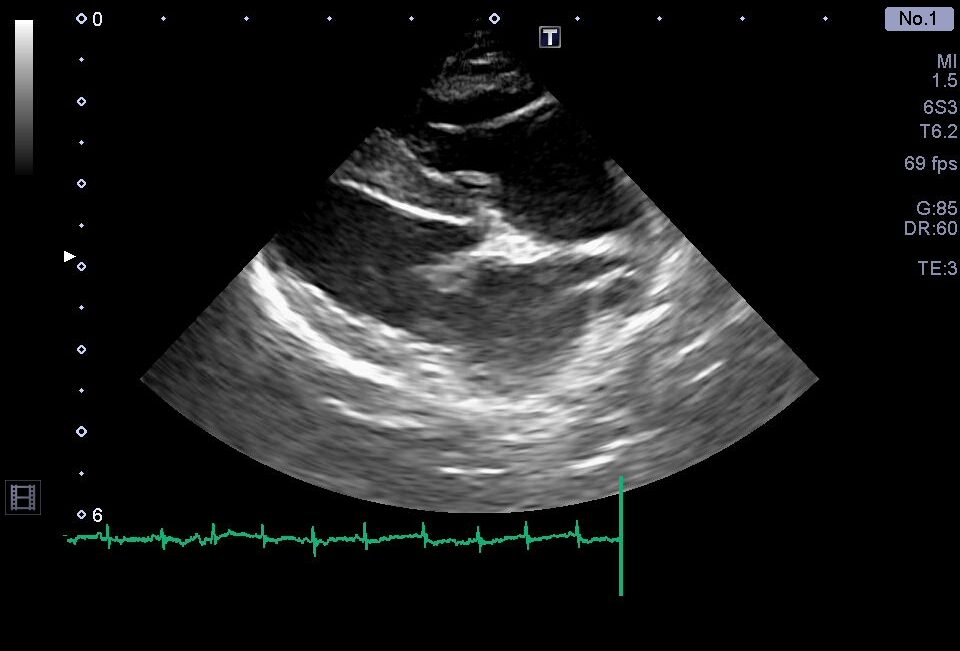

治療強化後の心臓超音波検査。右心系拡大の改善を認める。

心室中隔扁平化の改善

以前と比較して、三尖弁逆流速度の低下を認める

肺高血圧症に対する治療強化後の再診察では、上記のような心臓形態の改善を認めた他、呼吸の改善や腹水の顕著な減少を認めました。